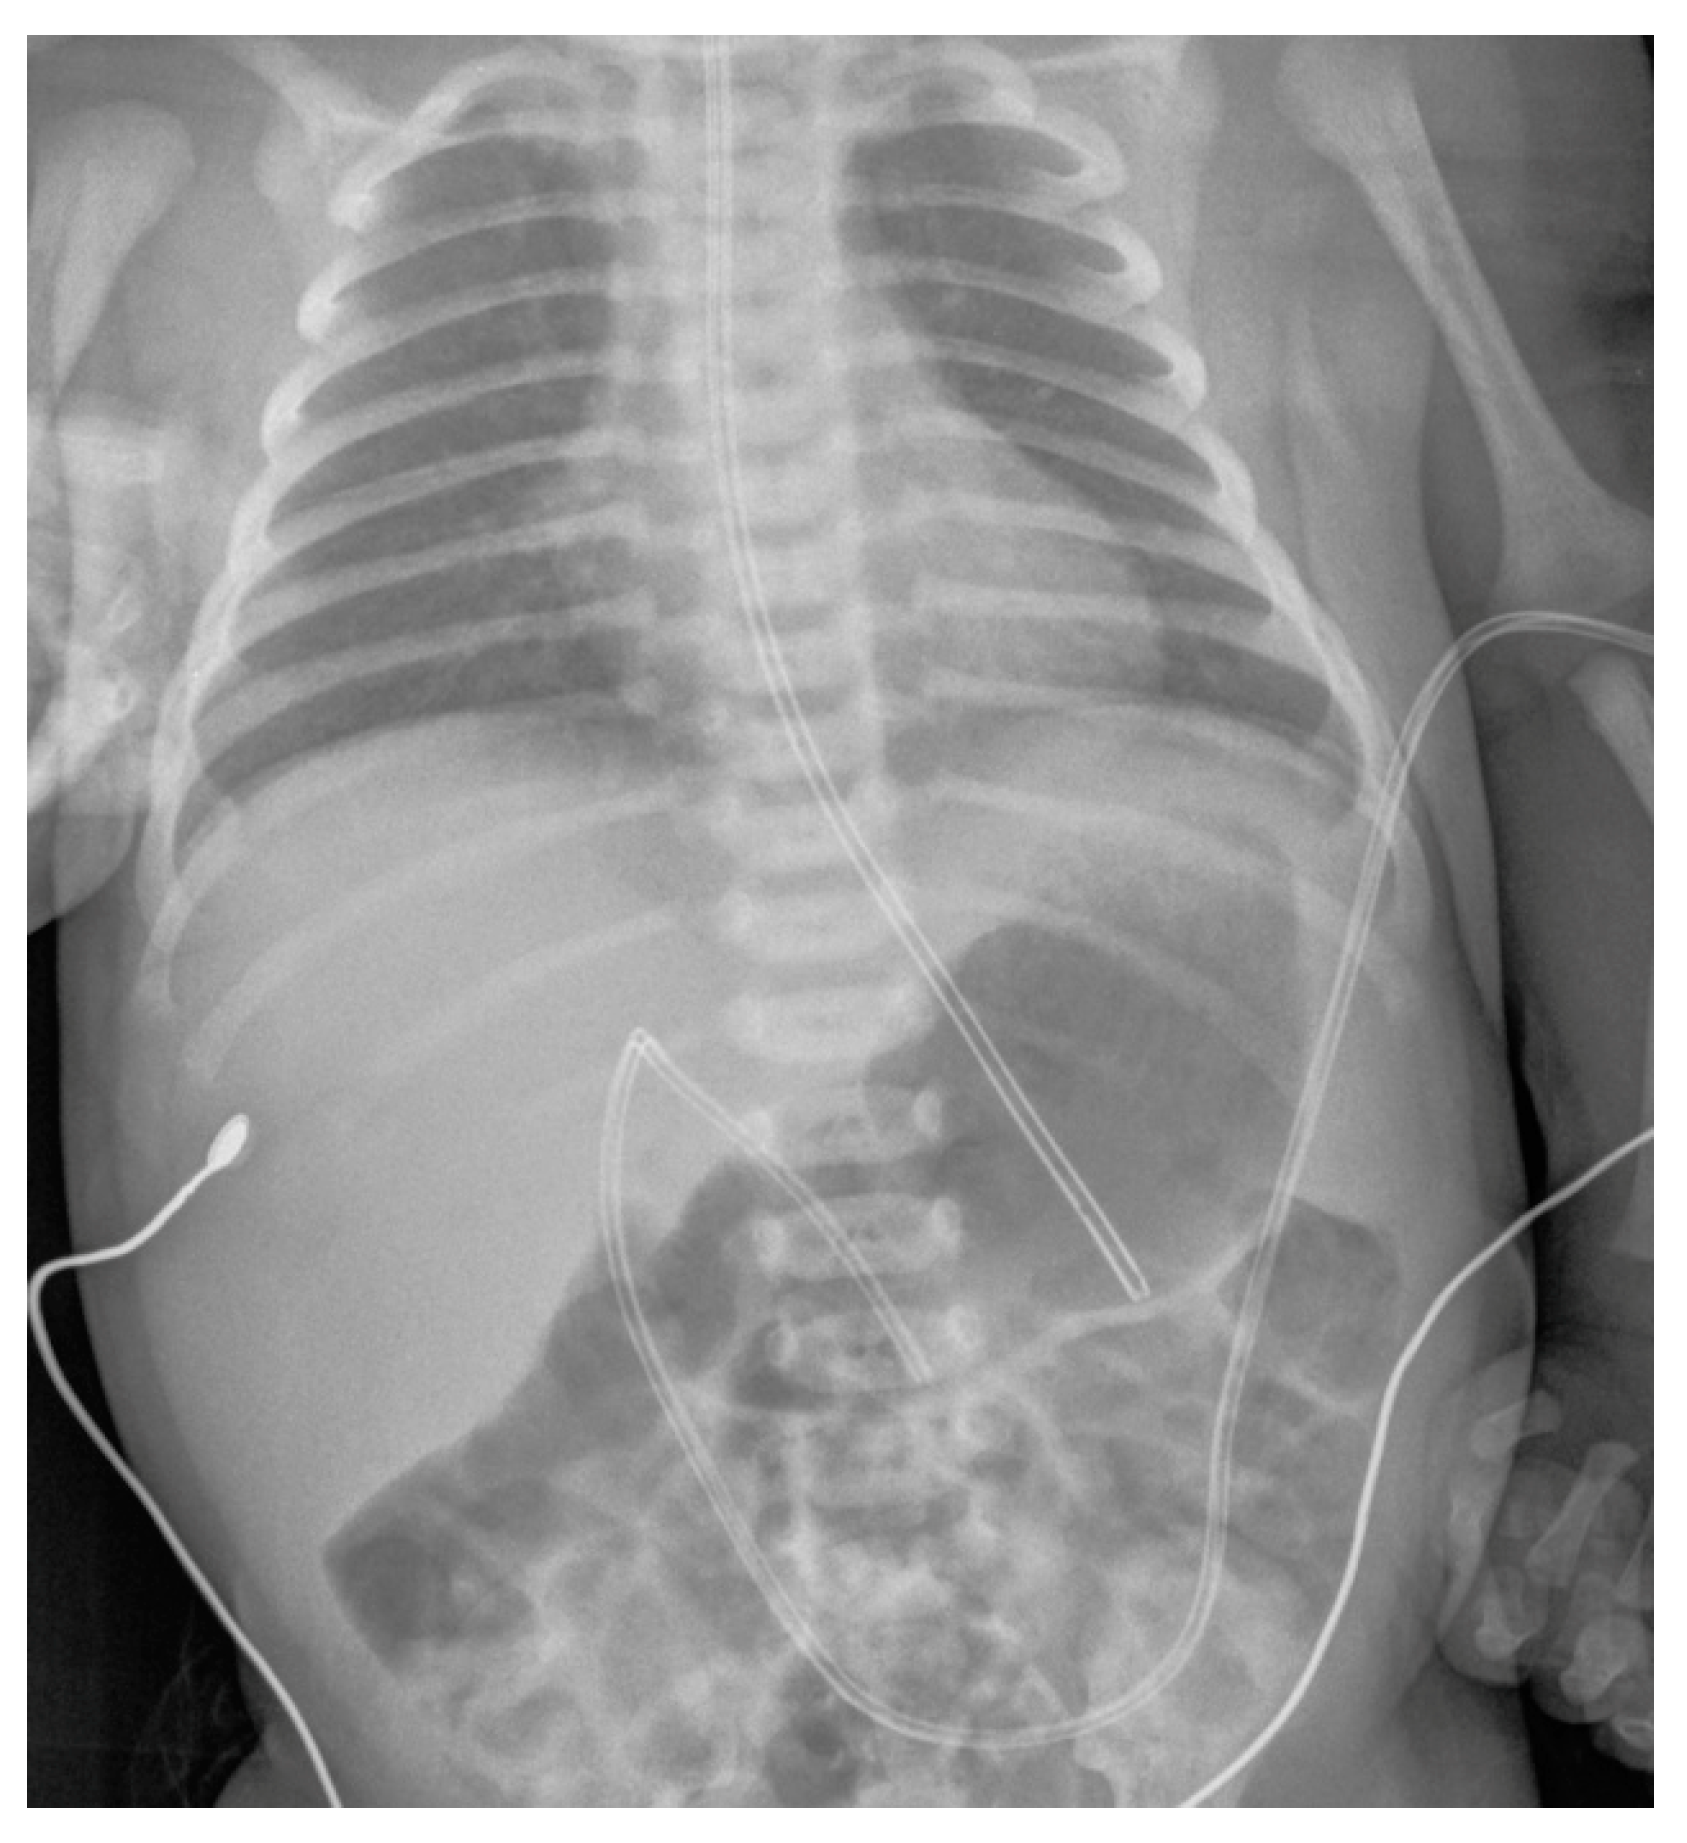

Conventional Radiology Evaluation of Neonatal Intravascular Devices (NIVDs): A Case Series

3. Results